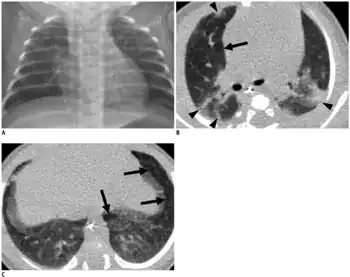

| An X-ray showing bronchopulmonary dysplasia. Person is also intubated and has an oral gastric tube. | |

- CXR shows with hyperinflation, low diaphragm, atelectasis, cystic changes.